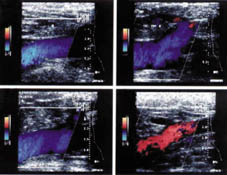

Cayado safeno interno: Se observa

cambio de color a nivel del cayado safeno interno, en la imagen

inferior derecha, que representa reflujo a este nivel.

Venas perforantes:

Se aprecia vena perforante que comunica venas gemelares con el sistema

safeno interno, en sentido longitudinal.